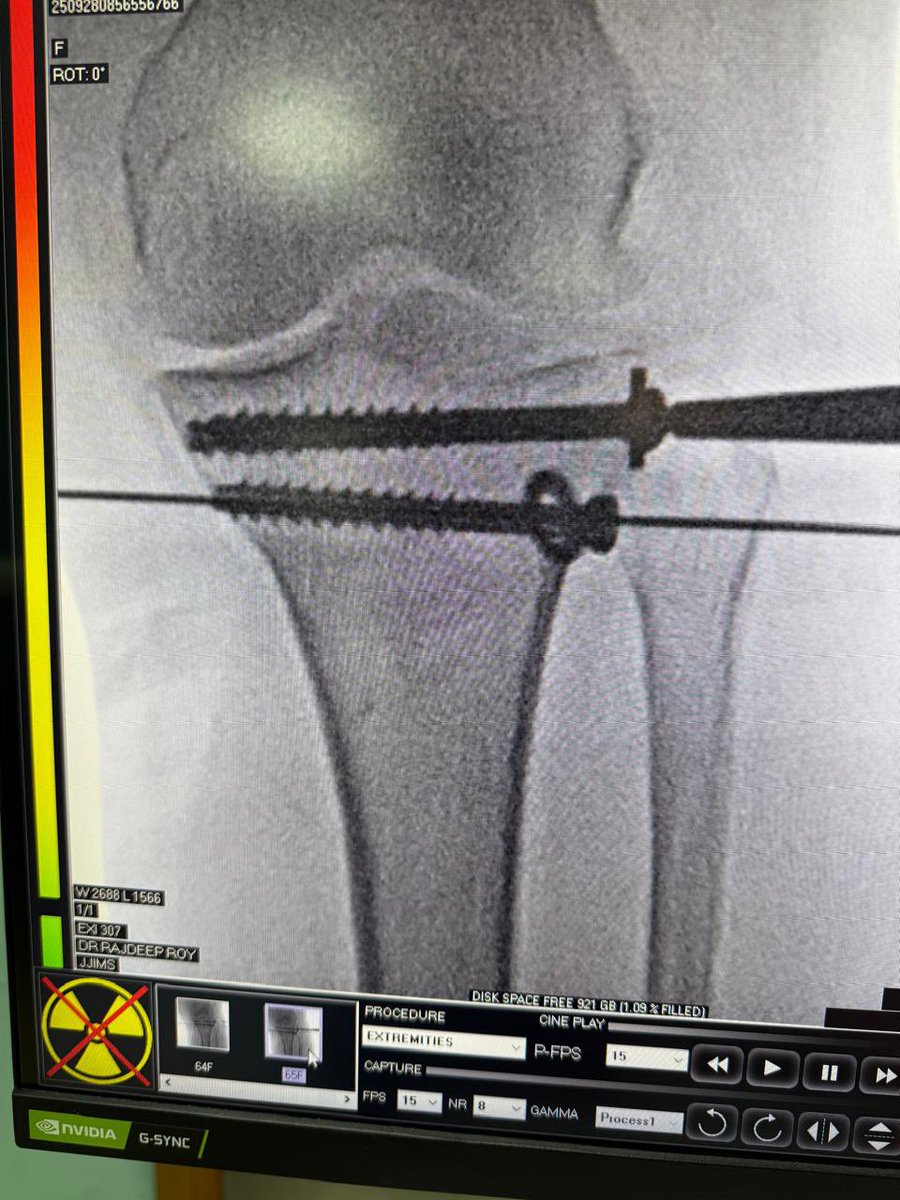

Minimally Invasive Percutaneous surgeries are being performed by our Ortho teams regularly keeping in mind early mobilisation , less hosp stay and minimal cost. @drrajdeeproy #IntraArticularFracture

@drrajdeeproy operated on a complex proximal tibia fracture ( Shatzkar Ty Vl ) A planned and good physio is an integral part of treatment procedure and it helps achieve desired result in such fractures ! @BritOrthopaedic @AAOSAdvocacy @IndianOrthAssoc ROM at 6 was 👇

Biological fixation achieved by @drrajdeeproy and team. MIPPO ( Minimally Invasive Percutaneous Plate Osteosynthesis ) in a70yr/M. Benefits : Micro incision Early recovery Less hosp stay Early return to work. @AAOSAdvocacy @BritOrthopaedic @IOA